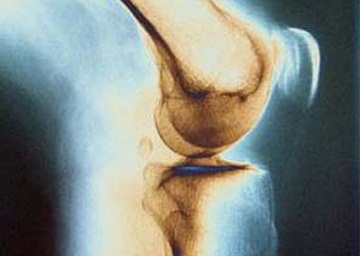

بیماری استخوان مدتها قبل از بروز علائم آغاز میشود. به این علت معمولا با نام فلج کننده خاموش شناخته می شود. تنها راه اطلاع از بروز این بیماری انجام آزمایش است. پزشک شما تعدادی آزمایش برای چک کردن سطح مواد شیمیایی در بدن که بر سلامت استخوانها موثر هستند، انجام میدهد. تجویز پزشک ممکن است شامل مواردی مانند آزمایش خون برای چک کردن کلسیم، فسفر، هورمون پاراتیروئید و ویتامین D، اسکن تراکم استخوان یا اشعه ایکس و نمونهبرداری از استخوان باشد.

بیماری کلیوی افراد را در معرض ابتلا به درد استخوان یا مفاصل، شکستگی استخوان، عفونتها و بیماری پوستی قرار میدهد. عواملی که موجب ضعف استخوان میشوند میتوانند خطر ابتلا به حملات قلبی را نیز به همراه داشته باشد. برای پیشگیری یا درمان بیماری استخوان با پزشک خود مشورت کنید. گامهای سادهای از بروز بیماری استخوان جلوگیری میکنند، مانند تغییر در رژیم غذایی.